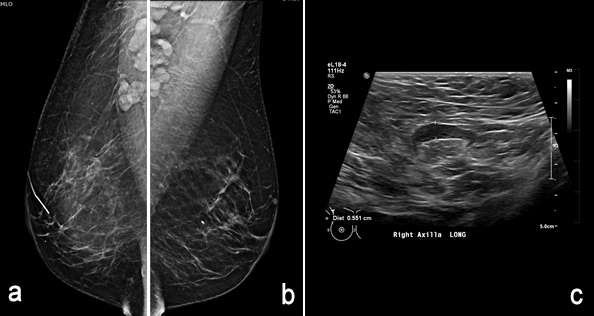

Figure 5, a-c.

Case: Axillary Lymphadenopathy  Figure 5

Figure 5: 61-year-old female with history of right ductal carcinoma in situ (DCIS) status post lumpectomy called back on screening mammogram for prominent lymph nodes bilaterally. Diagnostic mammogram demonstrates post-surgical changes in the right breast and biopsy marker in the left breast. There is bilateral axillary adenopathy (figure 5 a, b). Axillary ultrasound was performed which showed bilateral enlarged lymph nodes. Enlarged right axillary lymph node with cortical thickness measuring 6mm is shown (figure 5c). This correlates with known history of chronic lymphocytic leukemia (CLL) and was subsequently assigned BIRADS 2.